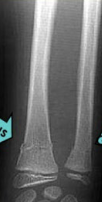

Trimalleolar

What is a trimalleolar fracture?

Fracture of ankle joint involving medial and lateral malleoli and posterior lip of distal tibia